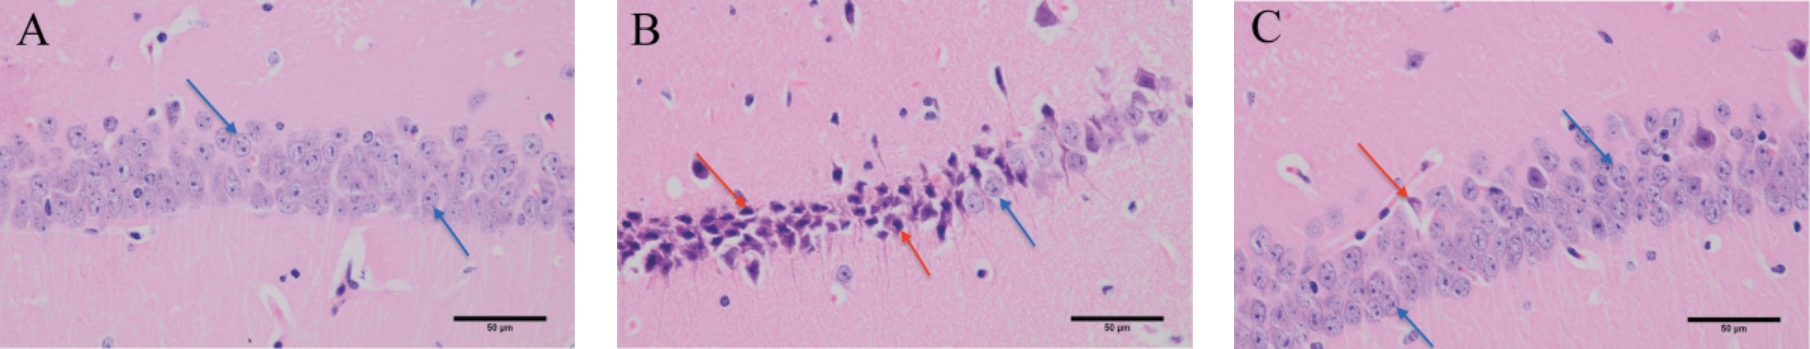

• HSP90介导线粒体分裂抗阿尔茨海默病的作用机制研究

2025, 35(14):31-37. DOI: 10.3969/j.issn.1005-8982.2025.14.006

摘要 (309) HTML (115) PDF 2.05 M (120) 评论 (0) 收藏

摘要:目的 以HSP90/PGAM5/DRP1通路为切入点,探讨其介导线粒体分裂抗阿尔茨海默病(AD)的作用机制。方法 将小鼠随机分为3组:对照组(C57BL/6J)、模型组(APP/PS1双转基因)、HSP90抑制剂组(模型+HSP90抑制剂干预)。通过Morris水迷宫实验评估小鼠学习记忆能力;HE染色观察海马组织病理形态;ELISA检测血清肿瘤坏死因子-α(TNF-α)、白细胞介素-4(IL-4)水平;免疫组织化学染色检测p-MLKL阳性表达;Western blotting检测海马组织Tau蛋白磷酸化、HSP90/PGAM5/DRP1通路相关蛋白表达。结果 模型组小鼠逃避潜伏期长于对照组(P <0.05),穿越平台次数少于对照组(P <0.05);HSP90抑制剂组小鼠逃避潜伏期短于模型组(P <0.05),穿越平台次数多于模型组(P <0.05)。海马组织出现病理性改变。模型组小鼠海马组织p-MLKL阳性表达量高于对照组(P <0.05);HSP90抑制剂组小鼠海马组织p-MLKL阳性表达量低于模型组(P <0.05)。与对照组相比,模型组小鼠海马组织IL-4水平降低(P <0.05),TNF-α水平升高(P <0.05);与模型组相比,HSP90抑制剂组小鼠海马组织IL-4水平升高(P <0.05),TNF-α水平降低(P <0.05)。与对照组相比,模型组小鼠海马组织HSP90、PGAM5、p-MLKL/MLKL、p-Drp1/Drp1、p-Tau蛋白表达量均升高(P <0.05),MFN1、MFN2、ATP5a蛋白表达量均降低(P <0.05);与模型组比较,HSP90抑制剂组小鼠海马组织HSP90、PGAM5、p-MLKL/MLKL、p-Drp1/Drp1、p-Tau蛋白表达量均降低(P <0.05),MFN1、MFN2、ATP5a蛋白表达量均升高(P <0.05)。结论 HSP90/PGAM5/DRP1通路通过介导线粒体分裂参与AD进程,抑制该通路可显著减轻AD病理变化、抑制神经炎症并改善认知功能,为AD治疗提供新靶点。